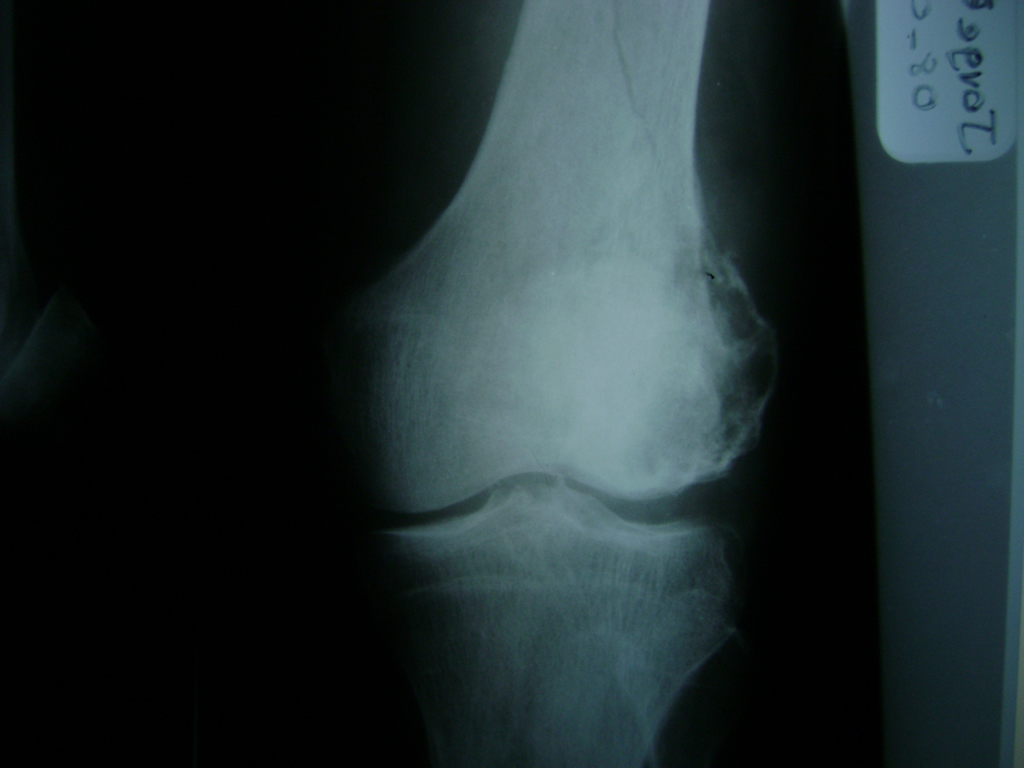

La artroscopia de rodilla es un cirugía en el cual la estructura interna de la articulación es examinada ya sea para realizar un diagnostico o para realizar un tratamiento, este procedimiento se realiza utilizando un instrumento parecido a un pequeño tubo llamado artroscopio.

La artroscopia se popularizo en 1960 y hoy en día es muy común en todo el mundo. Típicamente, es realizada por cirujanos ortopédicos de manera ambulatoria. Cuando se realiza de manera ambulatoria los pacientes pueden regresar a casa después de la operación, no se requiere quedarse en hospital.